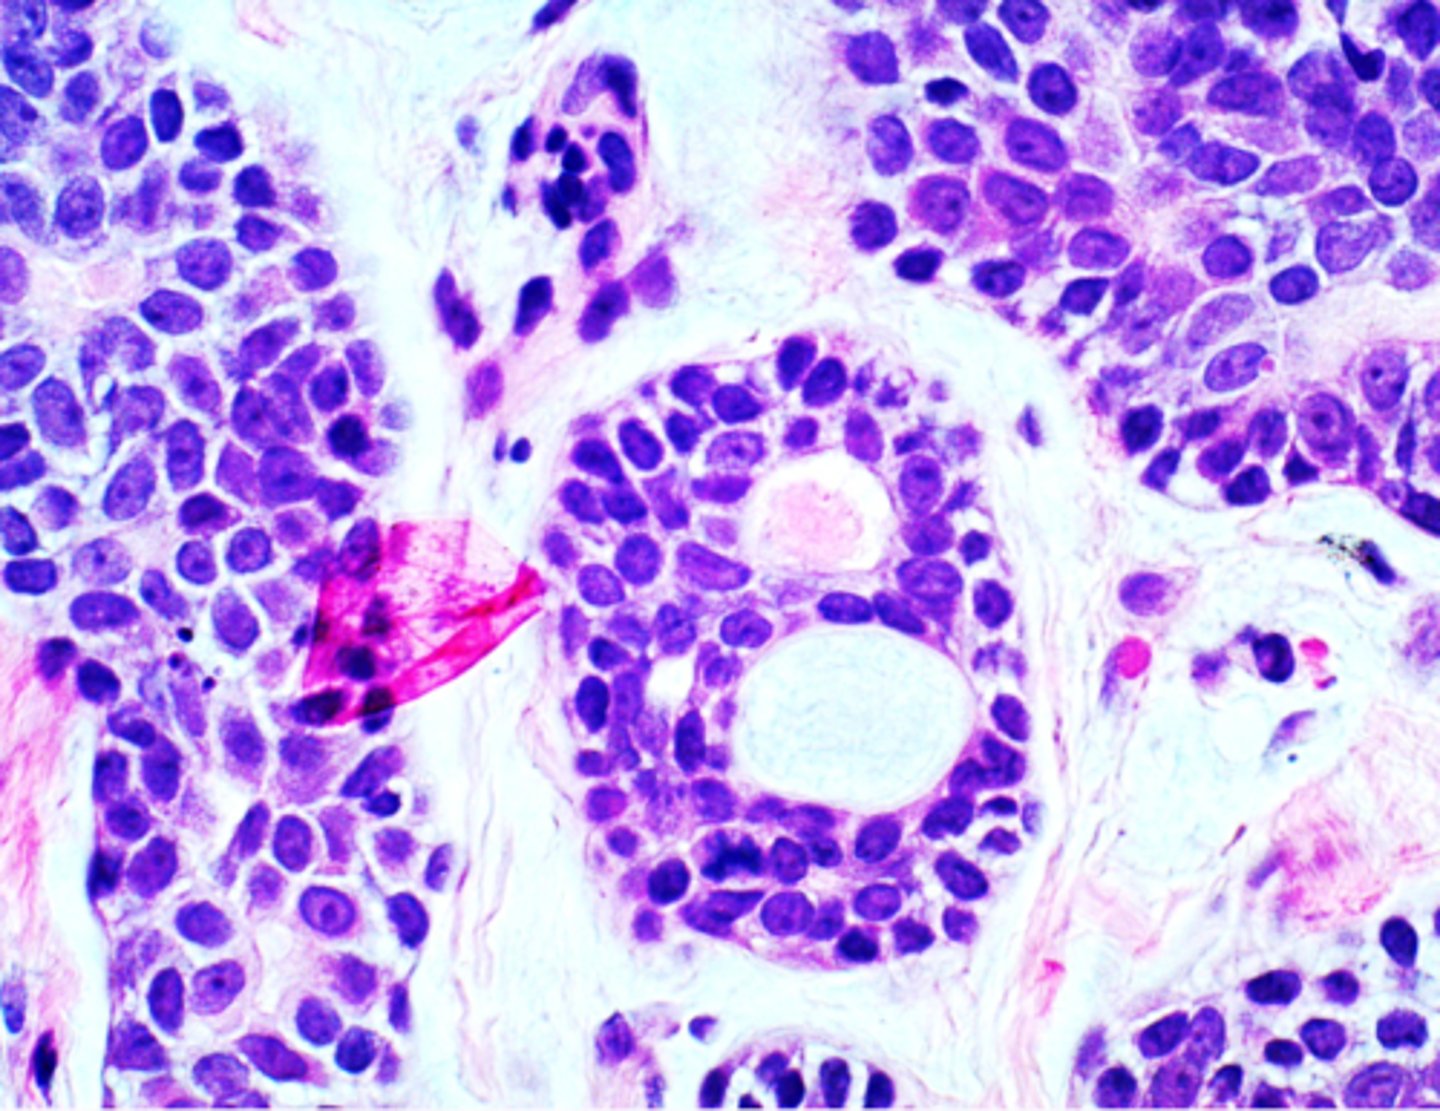

Mucoepidermoid Carcinoma

-Epidermoid cells

-Mucous cells

-Ductal structures

-Cystic spaces

-CRCT1-MAMl2 translocation ⇒ t(11;19)

• Swiss Cheese pattern

▫ Islands with a

cribriform pattern

▫ Myoepithelial and ductal cells are present

▫ Perineural and perivascular invasion